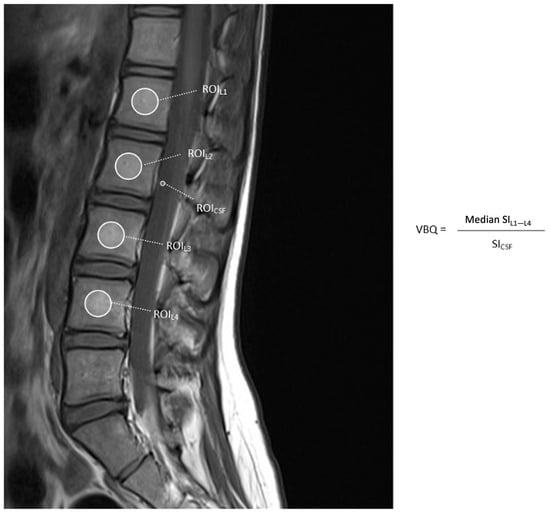

3.1. Vertebral Bone Quality Calculation